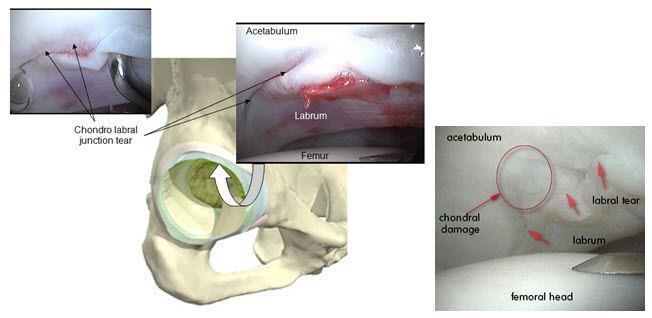

הלברום האצטבולארי

לפתח הגרמי של האצטבולום, צמודה טבעת סחוסית גמישה שנקראת הלברום האצטבולארי. טבעת זו מעמיקה את המכתש, מייצבת את ראש הירך בתוכו ואוטמת את מעבר הנוזל בתוך הפרק בצורה שמייעלת את פיזור הכוחות שמופעלים על הסחוסים.

במצבים בהם מביאים את הירך לטווחים קיצוניים, אנו עלולים לכתוש את הלברום בין שני צדי המפרק כאשר צוואר הירך צובט את הלברום שיושב על הגבול של האצטבולום ובכך גורם לנזק שעלול לפגום ביכולת שלו לייצב ולאטום.

בנוסף, הלברום הוא המשכי לציפוי הסחוסי של האצטבולום, כך שפגיעה בו עלולה לגרום לנזק בסחוס הסמוך לבסיסו.

תסמונת התפס הפמורו אצטבולארית

שינויים במבנה האנטומי של מפרק הירך יכולים להביא ל"התנגשות" מוקדמת בין שני הצדדים וכך לגרום נזק ללברום ולסחוס. לקונפליקט בין ראש הפמור האצטבולום אנחנו קוראים "תפס" או "צביטה" (ובאנגלית, impingement).

באופן כללי, ישנם שני סוגים עיקריים של תפס: האחד נובע מבליטה של ראש הפמור ונקרא cam type, והשני נובע מבליטת הקיר של פתח המכתש האצטבולרי ונקרא Pincer type. בנוסף, חלק ניכר ממקרי התפס נגרמים משילוב של שני סוגים אלו.

דוגמאות לקרעים בלברום והטיפול בהם: